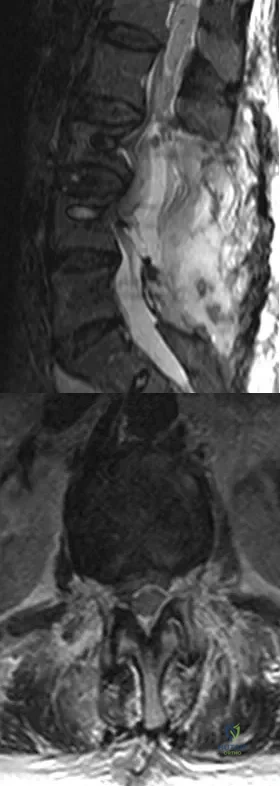

A 13-year-old girl sustained an isolated midshaft left femoral fracture in a motor vehicle accident. The fracture was treated with a rigid, antegrade intramedullary nail placed through the piriformis fossa. The fracture healed uneventfully, as shown in Figure 46a; however, at 12 months postoperatively she now reports left hip pain. A current AP radiograph and MRI scan are shown in Figures 46b and 46c. What complication occurred in this patient?

Options:

- Chondrolysis

- Ischemic necrosis of the femoral head

- Ischemic necrosis of the greater trochanter

- Femoral neck fracture

- Trochanteric overgrowth

Correct Answer: Ischemic necrosis of the femoral head

Explanation:

The development of femoral head ischemic necrosis is the iatrogenically created complication in this skeletally immature patient. Placement of a rigid, antegrade intramedullary nail through the piriformis fossa is likely to damage the vascular supply to the femoral head as the vessels ascend the femoral neck on the way to the femoral head. The MRI scan reveals ischemic necrosis with early collapse of the femoral head. The joint space is preserved on the MRI scan, ruling out chondrolysis. Letts M, Jarvis J, Lawton L, et al: Complications of rigid intramedullary rodding of femoral shaft fractures in children. J Trauma 2002;52:504-516. Buckley SL: Current trends in the treatment of femoral shaft fractures in children and adolescents. Clin Orthop Relat Res 1997;338:60-73.